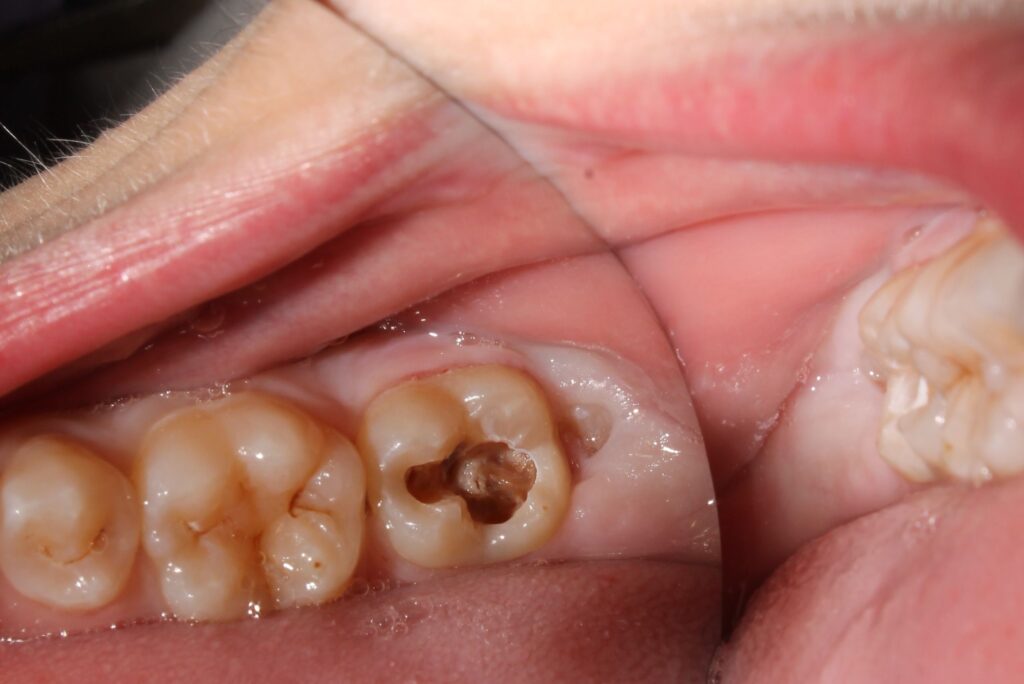

Una caries dental profunda es una lesión avanzada del diente que afecta las capas internas, llegando hasta la pulpa o quedando muy cerca de ella. Se origina por la acción continua de las bacterias que producen ácidos capaces de atravesar el esmalte y la dentina. Cuando esto sucede, el nervio puede irritarse e inflamarse, causando molestias intensas y sensibilidad.

A diferencia de las caries superficiales, que se limitan al esmalte, en este tipo de daño la estructura dental se debilita de forma considerable. Por eso, cuanto antes se trate, más probabilidades hay de conservar la muela y evitar la extracción o la infección del nervio.

Una muela con caries profunda se diferencia de una común por la extensión del daño y la intensidad de los síntomas. En las caries iniciales, el esmalte es el único afectado, y un empaste suele ser suficiente para frenar el problema. En cambio, cuando la lesión llega a la dentina o la pulpa, el dolor se vuelve constante y puede aparecer incluso sin estímulo externo.

- Manchas oscuras o cavidades visibles en la superficie del diente, especialmente en las muelas.